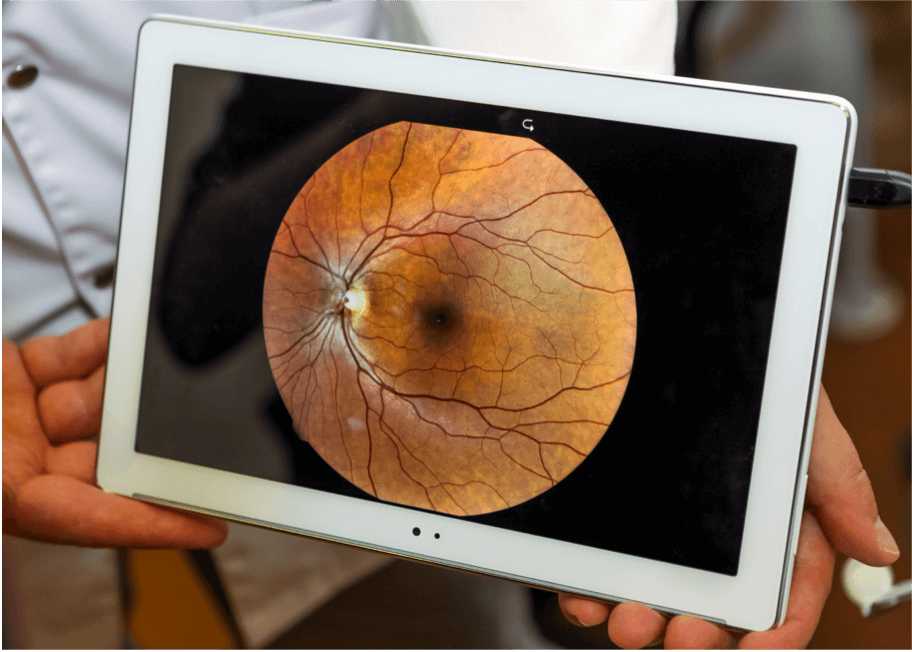

Fotografía del fondo de ojo

La fotografía del fondo de ojo se realiza con un microscopio de baja potencia para tomar imágenes en color de la retina.7 Se utiliza habitualmente en el diagnóstico de la DMAE, ya que muestra anomalías de la retina como drusas, anomalías pigmentarias, atrofia, hemorragias y acumulación de líquido.7 Las imágenes tomadas a lo largo del tiempo pueden compararse para monitorizar la evolución de la enfermedad.